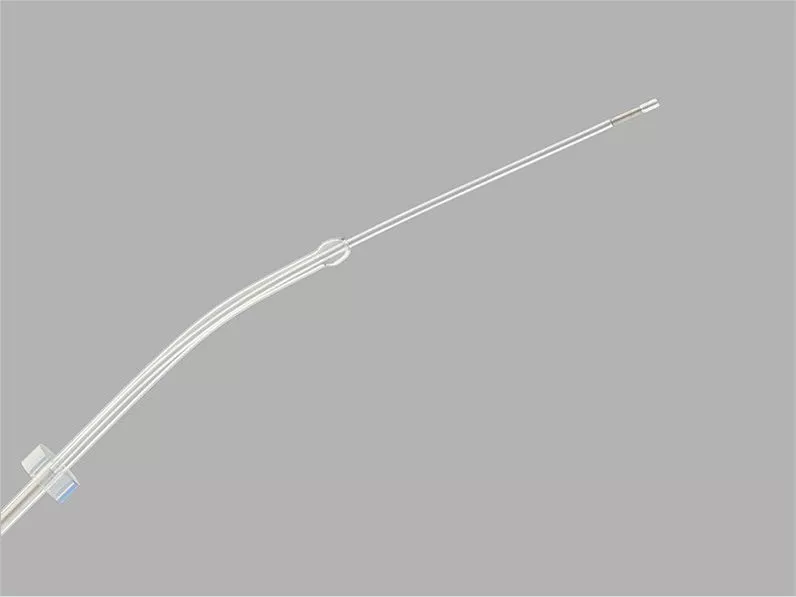

Guardia™ Access Nano Embryo Transfer Catheter

Guardia™ Access Embryo Transfer Catheter with Internal Support Cannula

Guardia™ AccessET Embryo Transfer Catheter

Guardia™ Access Embryo Transfer Catheter